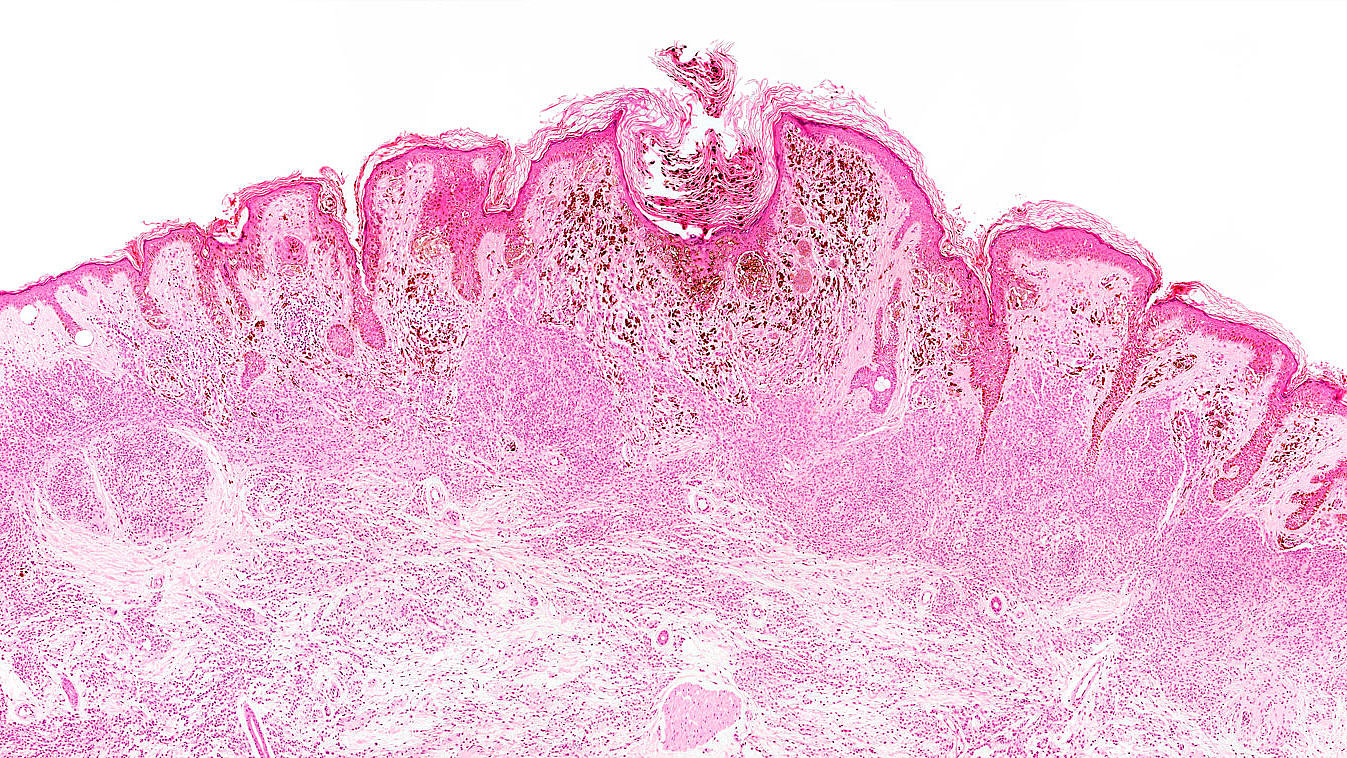

Basaliome und Plattenepithelkarzinome („weißer Hautkrebs“)

Zu dem sog. „weißen Hautkrebs“ gehören die Basaliome oder Basalzellkarzinome, die von der Basalzellschicht der Haut ausgehen. Sie sind der häufigste bösartige Hauttumor. Ebenfalls häufig treten Plattenepithelkarzinome, auch Spinaliome oder Spinalzellkarzinome genannt, auf. Experten schätzen, dass im Jahr 2014 etwa 169.100 Menschen an einem Basaliom und 49.400 an einem Plattenepithelkarzinom erkrankten. *1

Basalzellkarzinome metastasieren so gut wie nie und gelten daher auch als semimaligne (halbbösartig). Auch die Spinalzellkarzinome metastasieren erst recht spät (ab einer Größe von 1cm findet man gehäuft Metastasen), so dass beide Tumore in aller Regel ambulant, chirurgisch entfernt werden können. Nach der chirurgischen Exzision (Entfernung) wird das entnommene Gewebe unter dem Mikroskop untersucht, um den genauen Tumortyp festzustellen. Auch wird hierbei überprüft, ob auch alle Tumoranteile erfasst wurden.